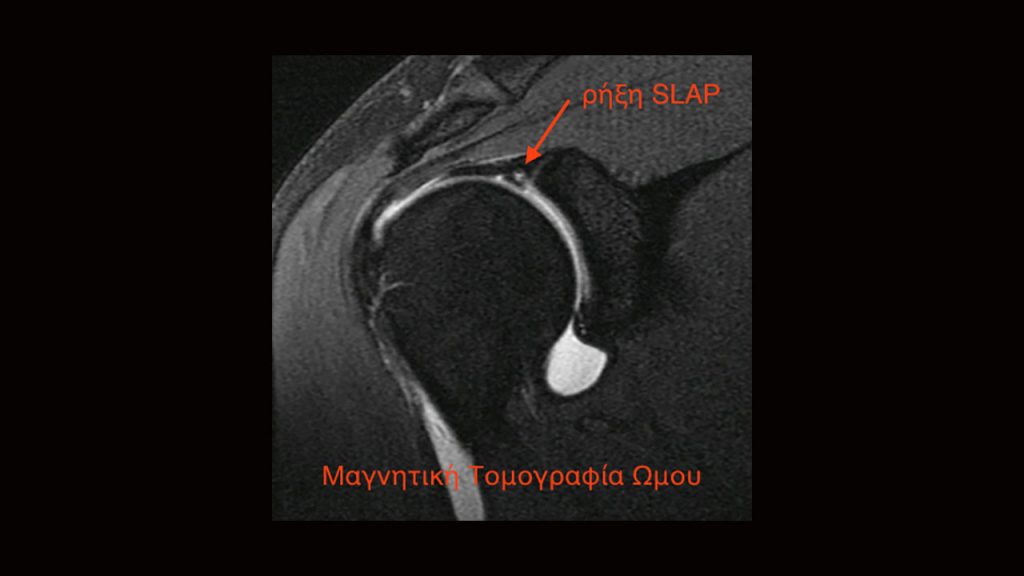

Στο άνω μέρος του επιχείλιου χόνδρου καταφύεται και η μακρά κεφαλή του δικεφάλου, η οποία είναι ο ένας από τους δύο άνω τένοντες του δικεφάλου μυός. Η ρήξη τύπου SLAP (πρόκειται για ακρωνύμιο που σημαίνει superior labrum anterior to posterior), δηλαδή ρήξη του άνω τμήματος του επιχείλιου χόνδρου αφορά αυτή ακριβώς την περιοχή.

Η διάγνωση γίνεται από το ιστορικό και τον κλινικό έλεγχο. Η απλή μαγνητική τομογραφία δεν έχει υψηλή ευαισθησία στην αναγνώριση της βλάβης. Η διενέργεια αυτής μετά από έγχυση στην άρθρωση σκιαγραφικής ουσίας αυξάνει την πιθανότητα ανεύρεσης της ρήξης. Βέβαια σε αρκετές περιπτώσεις η βλάβη αποκαλύπτεται τελικά κατά τη διάρκεια της αρθροσκόπησης.